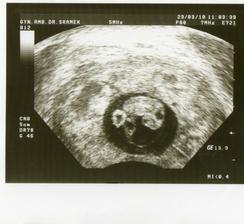

9.3 jsem zašpinila a tak jsem neváhala a jela na UTZ, kde mi doktor potvrdil že je tam jedno mimi a to špinění bylo asi ze ztráty druhého drobečka.

10.3. v noci krvácení - okamžitě nemocnice Jablonec, UTZ - Mimi je zatím OK. 15.3.- propuštěná vše OK 🙂 uuuf